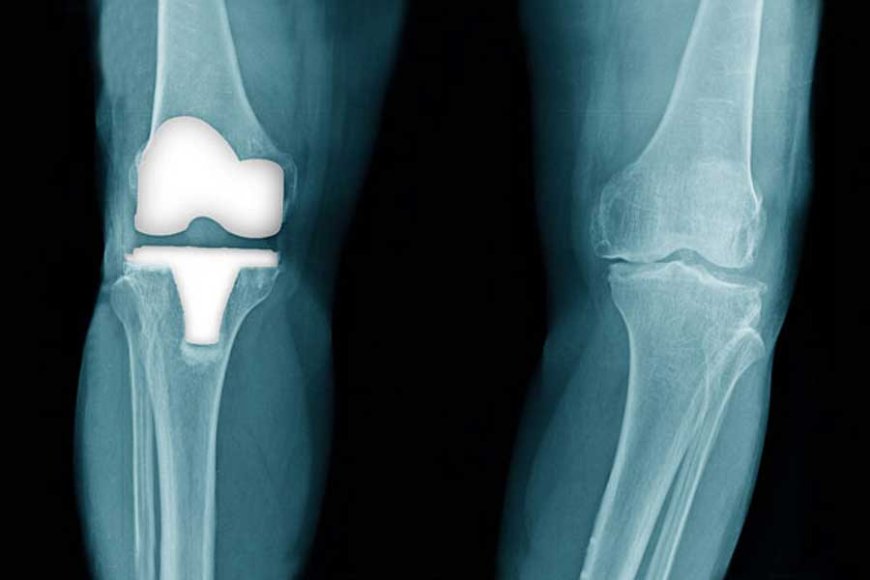

Knee pain can be life-limiting, affecting everything from your walk to your work. While Knee Replacement Surgery in Jaipur is an excellent option for advanced joint damage, many patients can avoid or delay surgery by adopting early interventions and lifestyle changes. As a leading orthopedic specialist, I believe prevention and timely care are just as important as surgical expertise.

While prevention is ideal, sometimes the damage progresses beyond conservative control. If daily activities are significantly impacted, Knee Replacement Surgery in Jaipur becomes the best solution for long-term relief and quality of life.